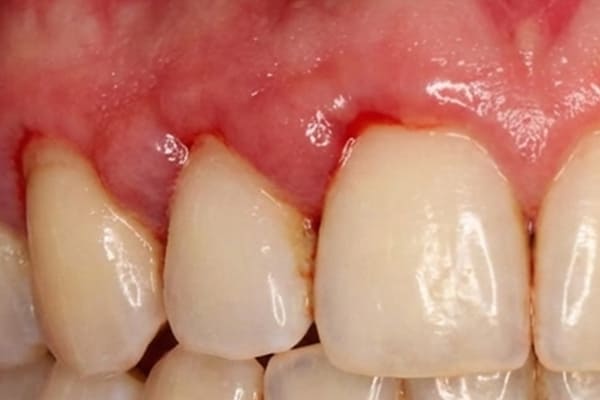

重度歯周炎 危険度★★★★★

重度の歯周炎になると、歯がグラグラして、歯と接している歯茎がさらに腫れ、化膿が進みます。歯と歯の間が広がり、歯茎が下がって、歯が長く見えます。

この段階の治療法は再生療法を用いて歯周組織の再生をはかることが多いです。しかし、ここまで進行すると抜歯になる可能性が高くなります。